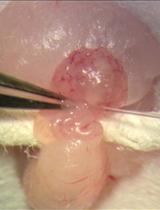

Cover of Pharmaceutical Research, featuring study using the protocol.

May 2019